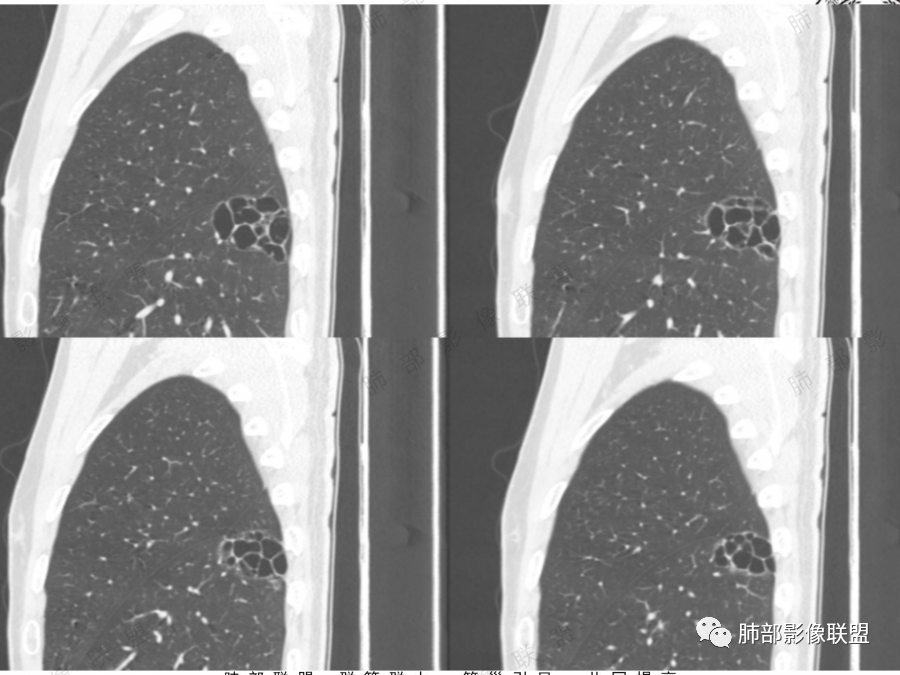

薄壁囊腔肺癌一般演变规律:

1.囊腔代表肿瘤生长的早期阶段;

2.囊壁逐渐增厚, 薄壁---囊壁增厚---GGO---实性;

3.经过有效治疗的厚壁囊性肺癌,可变为薄壁光滑的囊性肺癌。

5.病灶是否有分叶、毛刺、支气管截断、血管集束征、胸膜凹陷征等周围型肺癌的影像征象。应留意同侧肺门及纵隔有无增大淋巴结。

6.动态随访观察:初期囊腔病灶未出现明显恶性征象时诊断有困难,但是仍要引起足够的重视对病灶密切定期随访,如果随访中囊腔增大、囊壁不规则增厚、壁结节增大、囊腔消失呈实性病灶均应及时手术治疗。